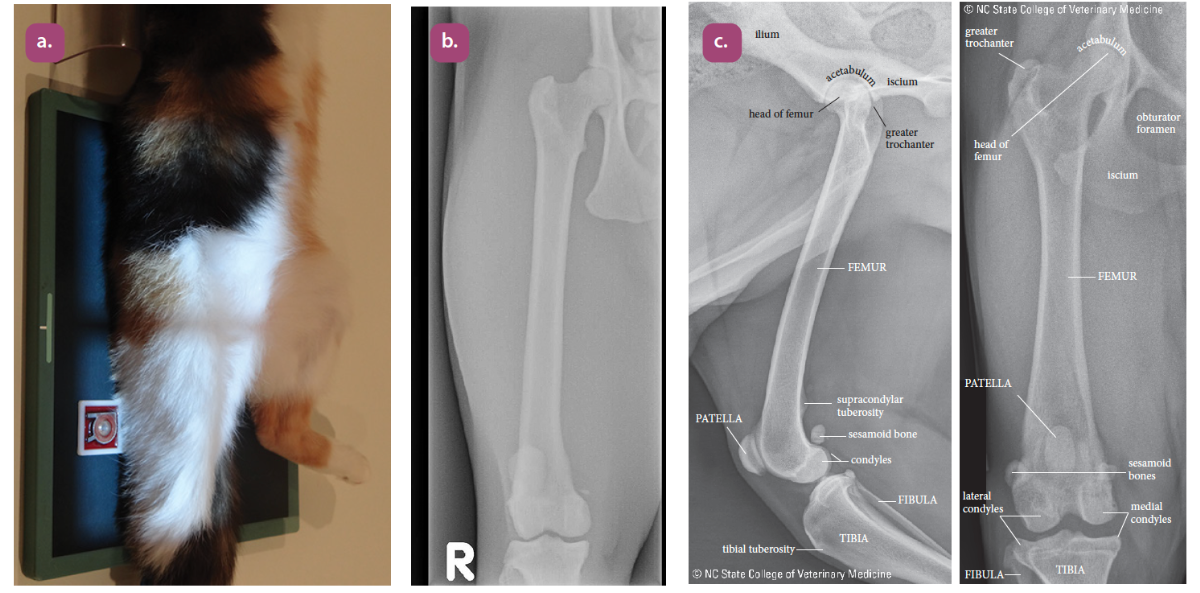

mediolateral projection of the femur

Craniocaudal projection of the femur